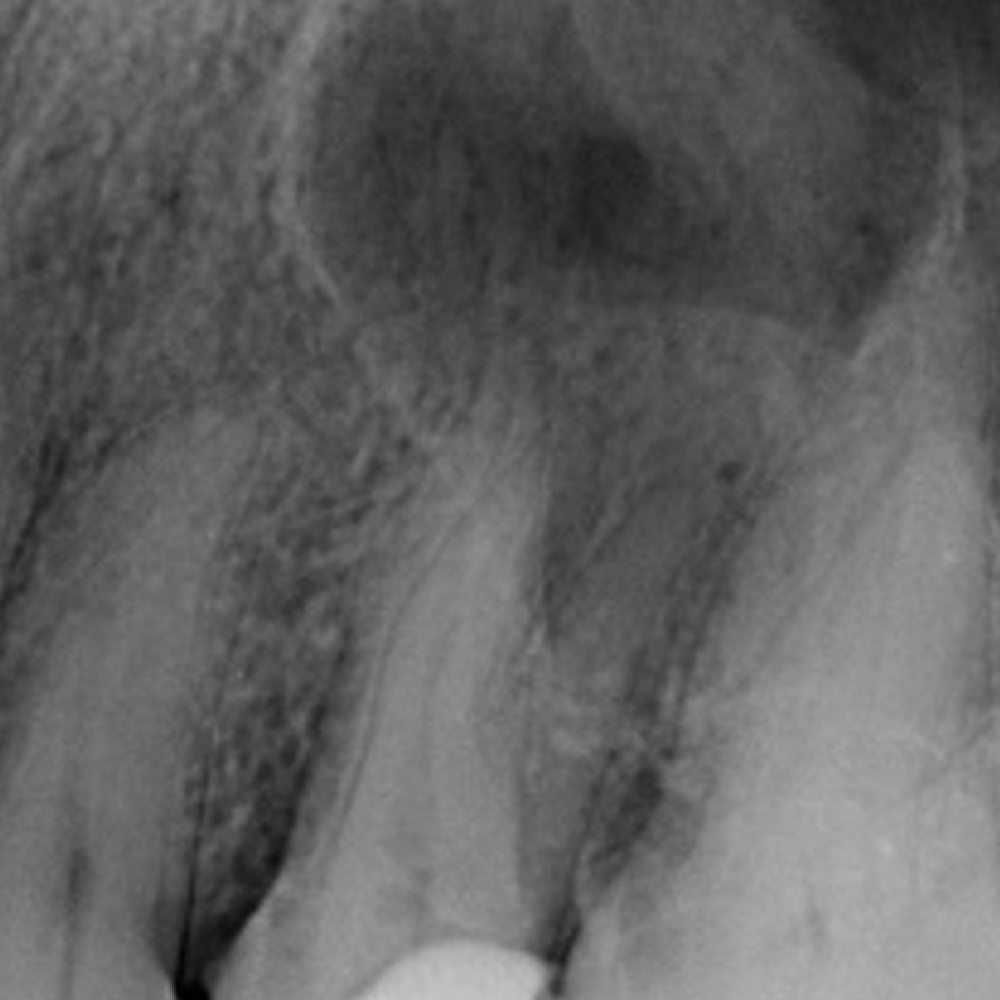

Before

After

Radix Entomolaris

3 Rooted Premolar

Re-RCT

Curved canals

Mulbery Molar

Molar with 6 canals